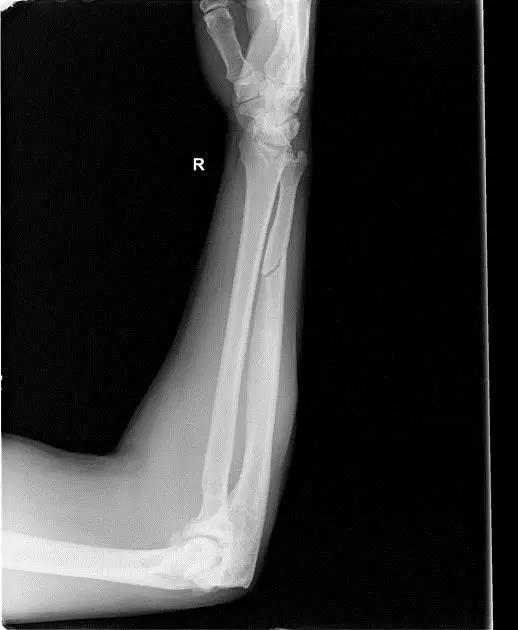

10. Galeazzi 骨折(盖氏骨折)

桡骨干下 1/3 骨折合并尺骨小头脱位。

盖氏骨折正侧位(来源:Orthobullets)